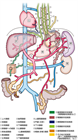

1. 食道・胃静脈瘤は慢性肝疾患などによる門脈圧亢進症に伴って代償的に形成される側副血行路の1つである。